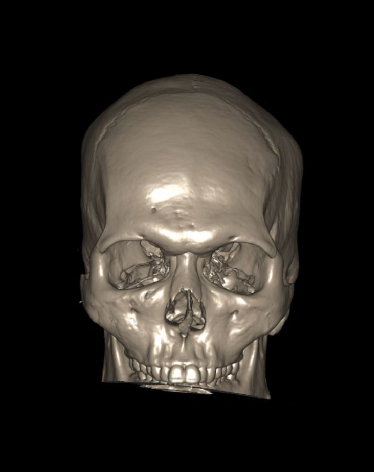

- 3d images to show fractures, dislocations or abnormalities.